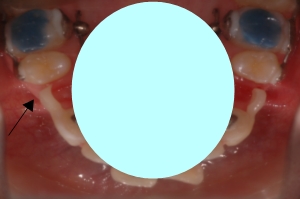

그러고는 저번에 발치하였던 왼쪽 발치공간에도 임시치아를 부착했습니다!

아! 이동할 공간을 위해 임시치아를 조금 갈아주었어요.